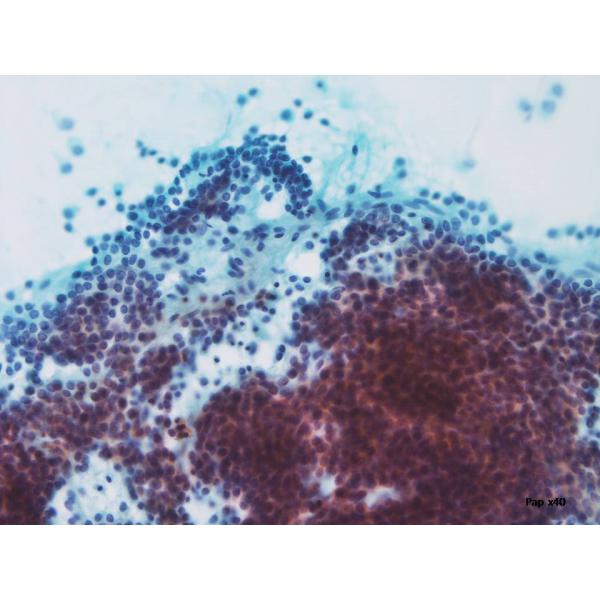

両下肢の有痛性紅斑と微熱、関節痛を主訴に当院皮膚科受診。結節性紅斑と診断され、ステロイド投与を開始。しかしステロイド減量すると症状の再燃を認め、膠原病内科で関節リウマチと診断。MTX使用するも症状の改善はない。画像検査で、左総~内・外腸骨動脈周囲と左鼠径リンパ節の腫脹と同部位にFDG集積を認めた。左鼠径リンパ節の穿刺吸引細胞診を行った。血液検査は、WBC 16600 (Neut 90%, Eosino 0%, Lym 5.0%, Aty-lymp 0%), LDH 187, sIL2-R 1069, HTLV-1は陰性。リンパ節生検がなされた。リンパ節のフローサイトでは、CD3: 29.7%, CD4: 76.0%, CD8: 4.2%, CD10: 1.0%, CD20: 22.4%, κ-鎖: 13.4%, λ-鎖: 11.0%, CD25: 6.6%, CD56: 0.6%であった。

穿刺吸引細胞診(#1-4)と捺印細胞診(#5,6)のpapanicolaou染色、Giemsa染色を示す。